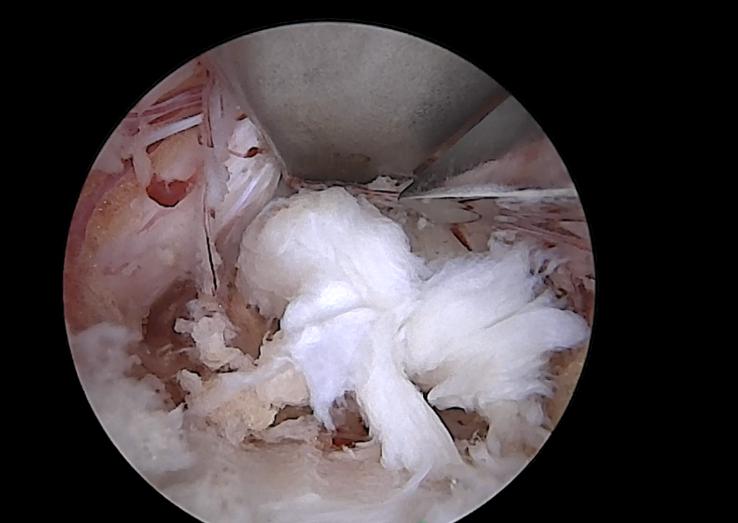

朱迪、王磊两位主任医师主刀,在内镜清晰、放大的视野监视之下,短短 1 个多小时,一直压迫神经根的椎间盘突出“顽疾”被精准无误地摘除了,手术部位切口1.5 厘米,仅一枚1角硬币大小,完美实现少出血、少剥离、高效率的预期效果。